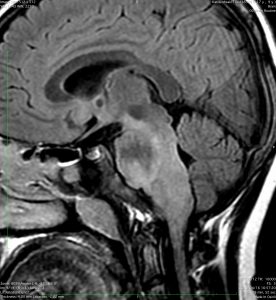

この脳幹部の橋グリオーマは小児に発生したものです。lateratityが強いと表現するのですが,左側に偏って存在しています。これは通常のびまん性橋膠腫では理解ができない画像ですから,生検術が必要かもしれません。でも病理確定診断がついたからといって,治療としてできることは50グレイくらいまでの局所放射線治療だけかもしれません。